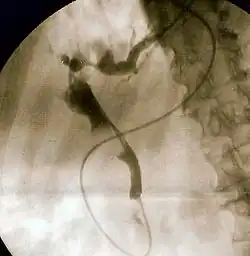

- Endoscopic retrograde cholangiopancreatography (ERCP)

- Transhepatic pancreato-cholangiography (TPC)

- To undergo ERCP for diagnosing diseases of biliary tree or their management